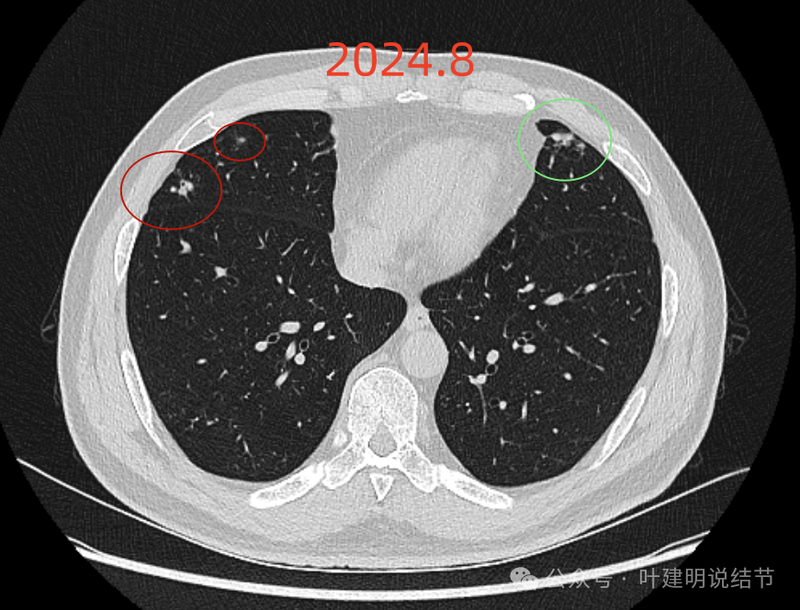

右中叶另处有斑点状多发实性结节,其中之一有小空泡征,也是轮廓与边界较为清楚的。

右中叶以及左上叶舌段也有多发偏模糊的实性结节影。